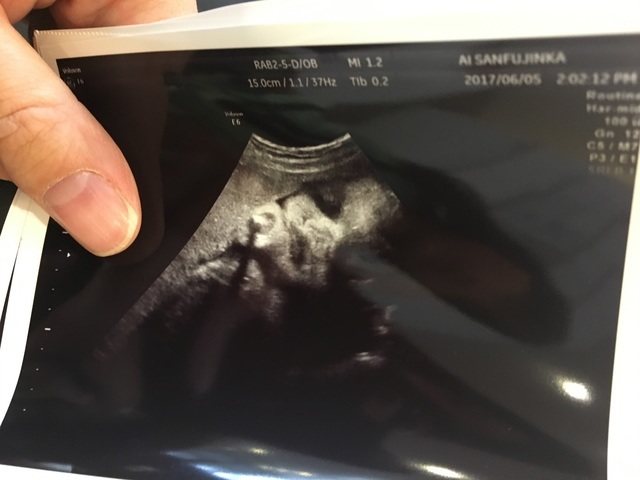

38週1日(38w1d・男の子)|あーかくん さん(24歳)

エコー写真撮影時のエピソード:

予定日前の最後の検診で赤ちゃんもいつ生まれてもおかしくない状態でのエコーだったので感極まりました。

結局生まれてきたのは予定日を5日すぎてからでしたが、パパもこの時のエコーははっきりシンボルがわかって女の子希望だったパパもすごくうれしそうでした!